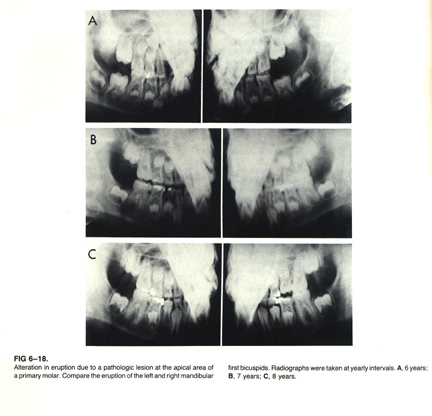

2. Eruption